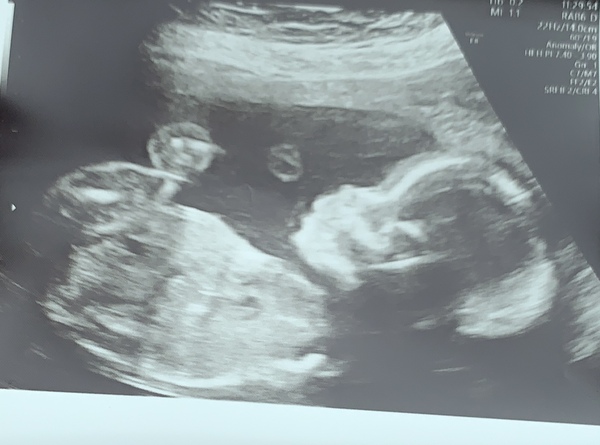

I had my 20 weeks scan today and I found out that we are having a baby boy!

So happy 😁 wahoo xx

Congratulations @Champson @Caz1226 on your scans, how lovely!

I had my 20 week scan yesterday and all was well with my baby girl. Considering it was April fools yesterday, I’m pleased to report that she’s still a girl 😂. Hoping to relax now and can’t wait for the shops to open to start buying things

Such a beautiful photo @Carefree1 💖😍 She's gorgeous.